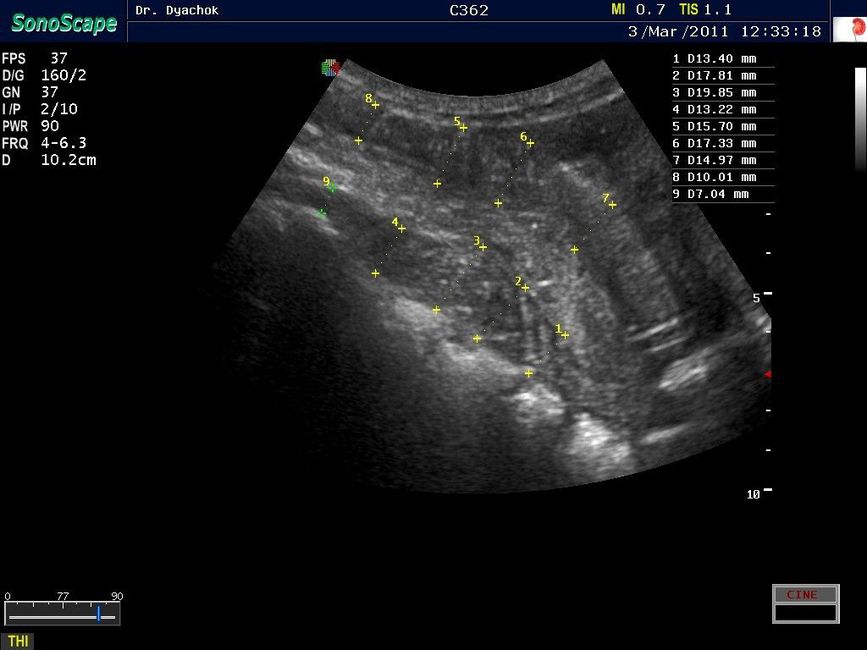

Sonoscape S9 представляет собой топовую переносную ультразвуковую систему, сочетающую инновационный дизайн, современные технологии визуализации и широкие диагностические возможности. Компактный аппарат экспертного класса подтверждает лидирующие позиции компании на рынке портативных ультразвуковых систем.

• Исследования поверхностных и абдоминальных органов